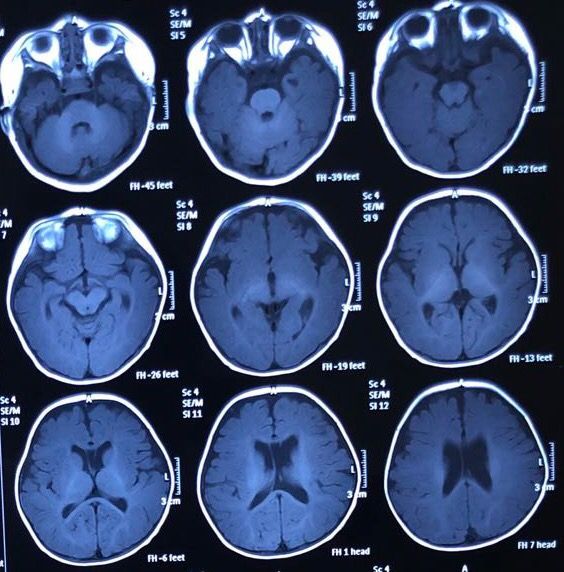

孕40周胎儿核磁共振

孕40周胎儿核磁共振

生后3月复查头颅核磁共振

生后3月复查头颅核磁共振